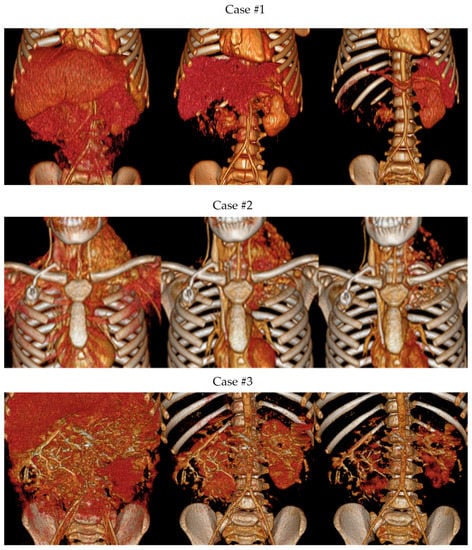

3.1.2. Volume Rendering and Cinematic Rendering

2.4.4. Cinematic Rendering